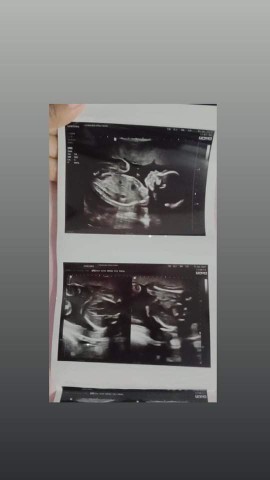

ซาวตอนน้อง20wk ตอนนี้36wkแล้วค้า😄